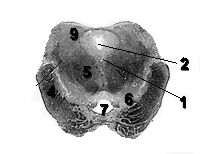

На поперечных срезах среднего мозга видно, что в толще холмиков крыши среднего мозга (colliuli tecti mesencephali) залегают скопления серого вещества, в верхнем холмике (colliculus superior) они называются серым слоем верхнего холмика (stratum griseum colliculi superioris), а в нижнем (colliculus inferior) – ядром нижнего холмика (nucleus colliculi inferioris). Серый слой верхнего холмика состоит из зрительных ядер, а ядро нижнего холмика – из слуховых.

Медиальнее расположен мозговой водопровод (aquaeductus cerebli), вокруг которого располагается центральное серое вещество (substantia grisea centralis). В его толще залегают ядра глазодвигательного и блокового нервов (nuclei nervi oculomotorius et trochlearis).

Вентральнее можно различить большие красные ядра (nuclei ruber) и черное вещество (substantia nigra). Эти структуры относятся к двигательной системе.

Рис. Поперечный срез среднего мозга на уровне верхнего холмика.

1. substantia grisea centralis

2. Aqueductus cerebri

4. Pedunculus cerebri

5. Nucleus rubber

6. Substantia nigra

7. Fossa interpeduncularis

9. Colliculus superior